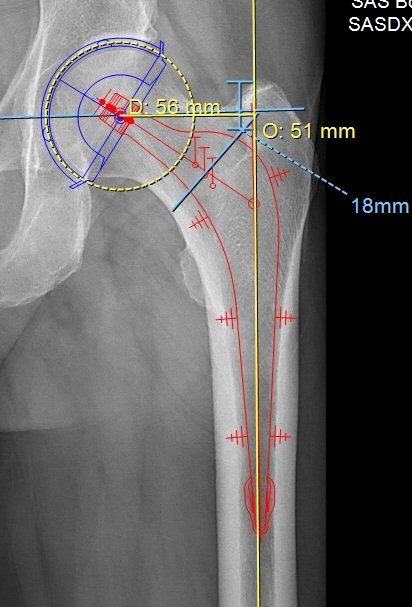

- Mät offset på frisk sida alt. gammal bild. Välj "Offfset" i "Ortho MSK", lägg linje i centrum av femur och kula med centrum i kaputs rotationscentrum. För att få korrekt värde så ska benet vara inåtroterat 15° på röntgenbilden.

- Man kan mäta från stammens skuldra till toppen av trokanter major. Under operationen kan man sedan mäta i såret för att se att stammen hamnat rätt, stammens skuldra ca 18 mm distalt om spetsen på trokanter major i exemplet nedan.

Kupp, stam, offsetmätning, osteotomilinje och mätning av stammens placering i djupled